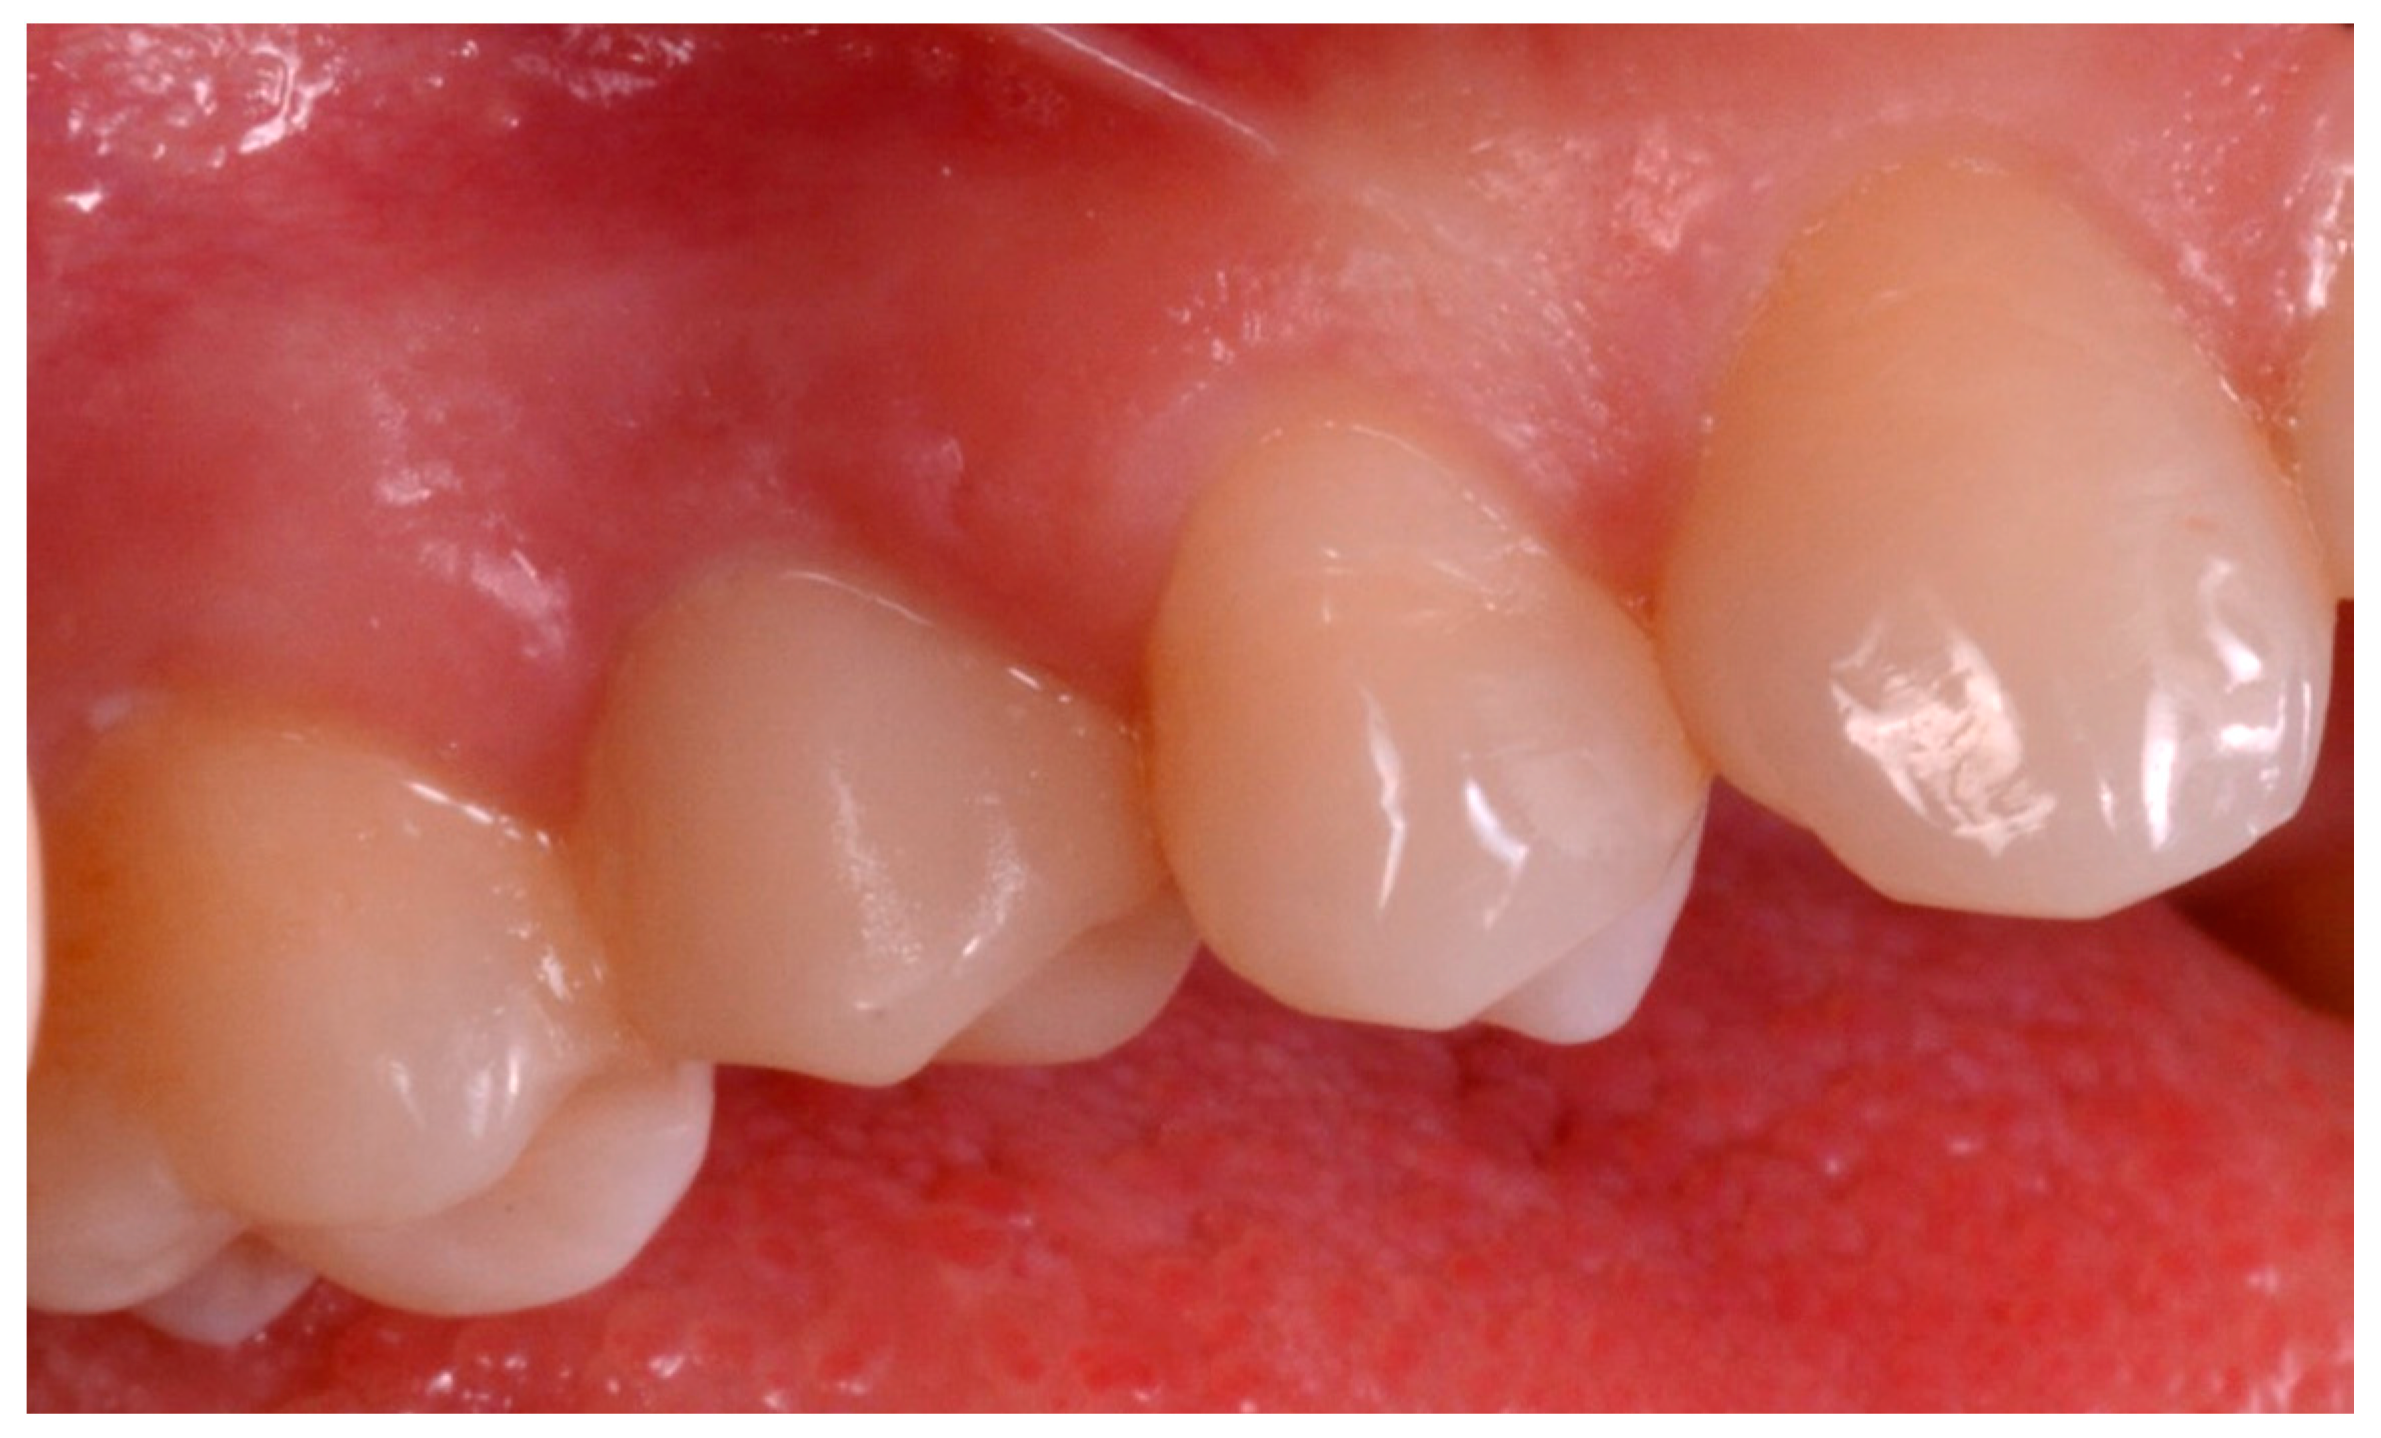

Figure 14.

Delivery of the final monolithic translucent zirconia restoration.

The 36 implants were successfully restored with 10 two-unit fixed partial prostheses and with 16 single crowns.

During the follow-up period and the provisionalization, two single crowns underwent a minor prosthetic complication, such as abutment-screw loosening. However, the abutments were screwed on the implants again and no further mechanical complications were reported for these fixtures. At the end of the study, the incidence of complications was 7.6% (2/26 restorations), but these complications were limited at the period of the provisionals.

At 1 year year after placement, all 36 implants were regularly functioning, for a survival rate of 100% (36/36 implants surviving) (Figure 15).